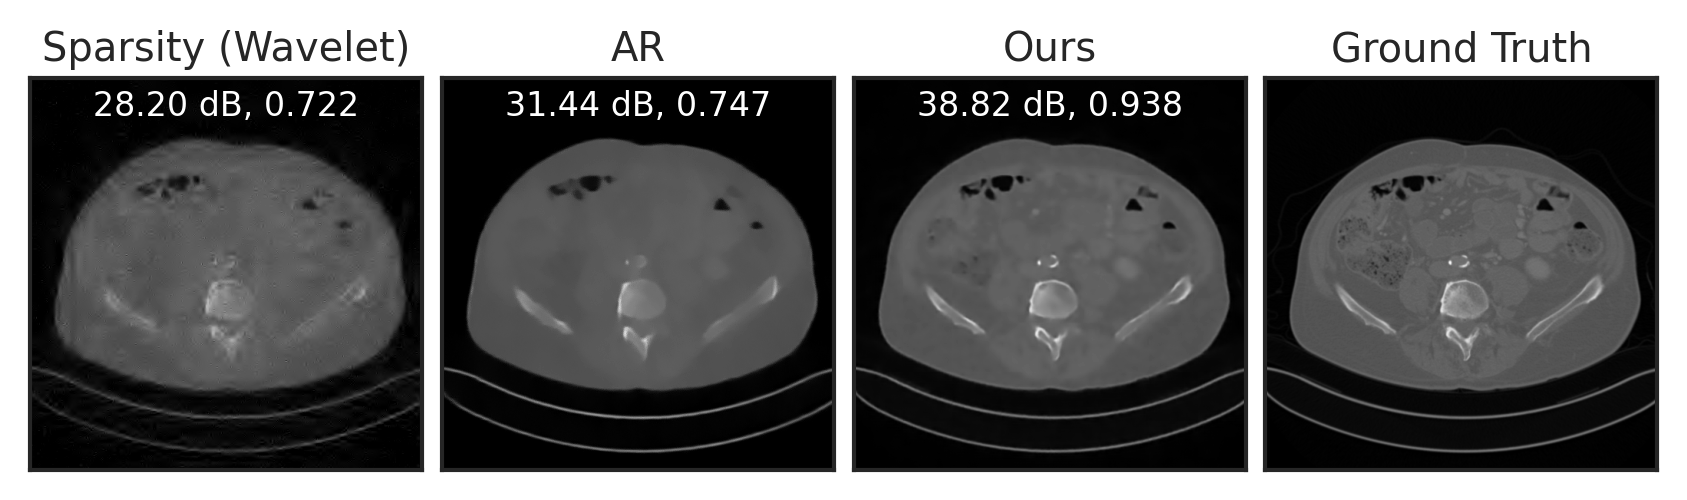

We train LPN on the public Mayo-CT dataset mccollough2016tu of Computed Tomography (CT) images, and evaluate it for two inverse tasks: sparse-view CT reconstruction and compressed sensing. For sparse-view CT reconstruction, we compare with filtered back-projection (FBP) willemink2019evolution, the adversarial regularizer (AR) method of lunz2018adversarial with an explicit regularizer, and its improved and subsequent version using unrolling (UAR) mukherjee2021end. UAR is trained to solve the inverse problem for a specific measurement operator (i.e., task-specific), while both AR and LPN are generic regularizers that are applicable to any measurement model (i.e., task-agnostic). In other words, the comparison with UAR is not completely fair, but we still include it here for a broader comparison.

Following Lunz et al. (2018), we simulate CT sinograms using a parallel-beam geometry with 200 angles and 400 detectors, with an undersampling rate of . See Section E.4 for experimental details. As visualized in Figure 4(a), compared to the baseline FBP, LPN can significantly reduce noise in the reconstruction. Compared to AR, LPN result is slightly sharper, with higher PNSR. The numerical results in Table 2 show that our method significantly improves over the baseline FBP, outperforms the unsupervised counterpart AR, and performs just slightly worse than the supervised approach UAR—without even having had access to the used forward operator. Figure 4(b) and Table 2 show compressed sensing results with compression rates of and . LPN significantly outperforms the baseline and AR, demonstrating better generalizability to different forward operators and inverse problems.